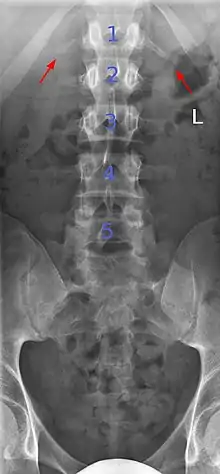

Butterfly vertebra (red). Normal vertebra for comparison (blue).

Volume rendering of a CT scan of the lumbar vertebral column, showing butterfly vertebrae at several levels, most typically in L1.